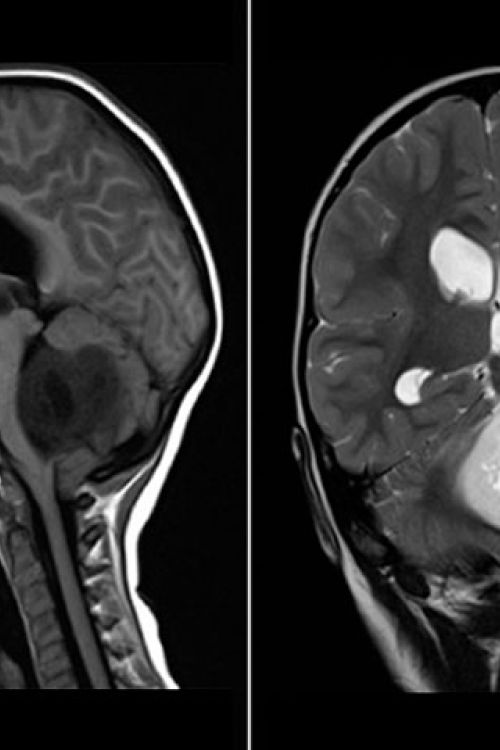

Análisis de intervención interdisciplinaria en niños con tumor de la fosa posterior Analysis interdisciplinary intervention in children with posterior fossa tumor